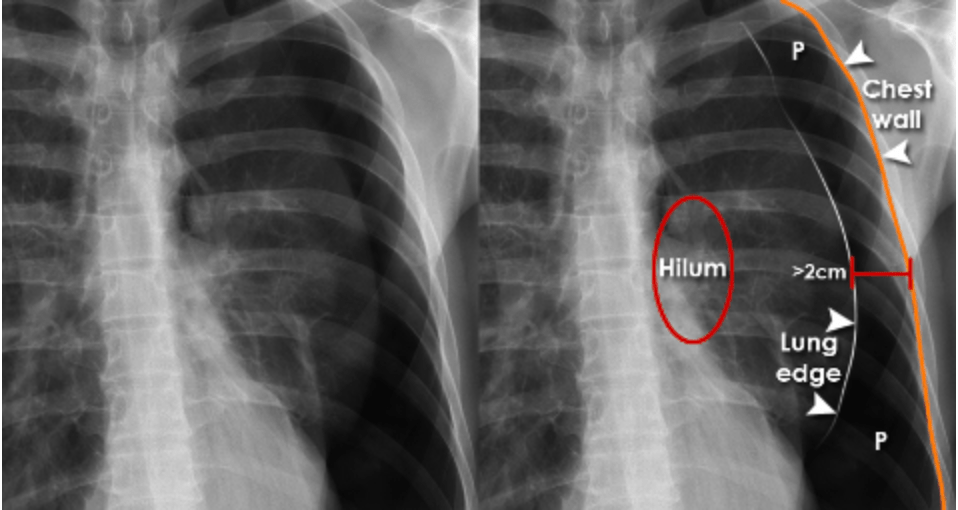

Answer: E) Simple pneumothorax

Explanation: A simple pneumothorax occurs when air enters the pleural space, causing lung collapse without mediastinal shift. Reduced breath sounds on one side and an absence of lung markings on X-ray confirm this. No tracheal deviation means it’s not tension pneumothorax.